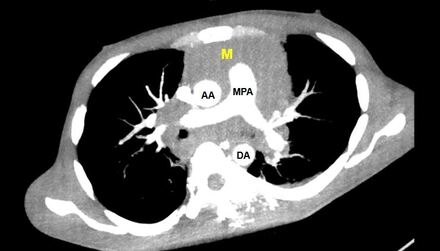

Case Presentation: ST-elevations on electrocardiogram are often due to cardiac emergencies such as a myocardial infarction. However, they may also signal a more occult pathology. A 35-year-old male with a past medical history of polysubstance-use disorder presented to the ED with a month-long history of chest and abdominal pain, and one day history of chest pain, orthopnea and respiratory distress. Initial vital signs significant for tachycardia to 124 bpm, otherwise normotensive, afebrile, and on room air. EKG notable for ST-elevations in the inferolateral leads. Ongoing symptoms, EKG changes, and elevated troponin prompted coronary angiography which showed no luminal disease. LVEDP was severely elevated (32 mmHg). Due to worsening respiratory distress, he was intubated and transferred to the cardiac critical care unit for suspected myocarditis. Cardiac MRI was significant for biventricular dysfunction (LVEF 30%, RVEF 32%), patchy late gadolinium enhancement (LGE) of both ventricles, and a well-circumscribed 15 mm x 15 mm region of LGE noted in the anterolateral myocardium consistent with an infiltrative mass, confirmed on CT chest imaging. Lymph node biopsy confirmed Classic Hodgkin Lymphoma. Incidentally, CT imaging of the abdomen also revealed a perforated abdominal viscous which was repaired laparoscopically. This surgery delayed systemic chemotherapy (ie high dose steroids) by 4 weeks. Patient was readmitted 3 weeks later with cardiogenic shock requiring vasopressors and intubation due to complete heart block and treated with a leadless pacemaker. Given this acute cardiac decompensation, endomyocardial biopsy was performed, revealing an aggressive B-Cell Lymphoma, thought to be a secondary primary lesion vs high-grade transformation. Patient underwent targeted radiation and multiple cycles of systemic chemotherapy, although course complicated by poor follow-up in the setting of polysubstance use and housing insecurity.